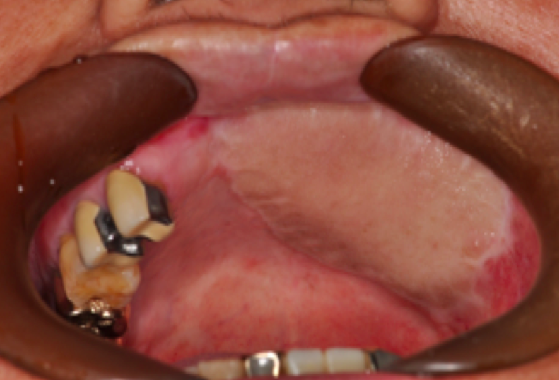

설암![]() |

치은암![]() |

구개암(입천정)![]() |

구강저암(혀아래)![]() |